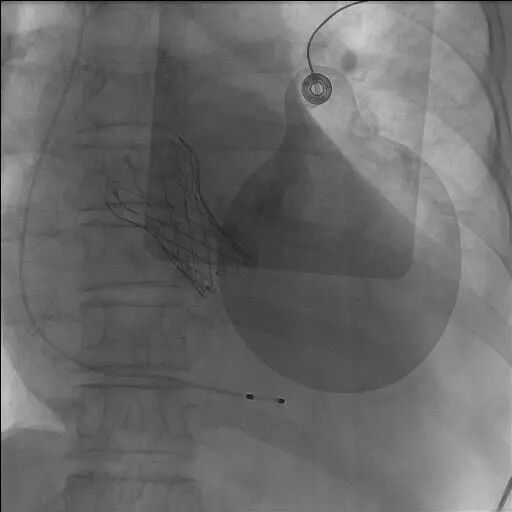

生死关头,在与患者家属充分沟通后,心血管诊疗中心一病区主任敖钦主任医师、主诊组长曹俊达副主任医师迅速集结心内、胸外、超声、麻醉、介入护理等多学科团队,并调动重症ECMO团队全程为手术保驾护航。团队选择经左侧颈总动脉入路,而这一术式,在急诊抢救、无术前CTA精准导航的双重极限条件下,无疑是一场超高难度的生死挑战。颈动脉是大脑供血命脉,操作稍有闪失即可引发灾难性卒中;无CTA就无法评估血管内斑块、走行异常、主动脉弓部情况,每一步都是“雷区”。心胸外科诊疗中心陈世雄副主任医师团队精准暴露左侧颈总动脉,穿刺、置管一气呵成。术中仅凭食道超声即时评估选择瓣膜型号,导丝“盲穿”穿过主动脉弓进入左心室。从穿刺到瓣膜释放,全程仅用时13分钟。造影显示瓣膜位置完美,无瓣周漏,冠脉通畅。术后患者血压即刻改善,次日心功能明显恢复,第五天转回普通病房,康复顺利。

经颈总动脉TAVR是国际指南推荐的非常规入路首选方案,具有路径短直、操控性好、血管易处理等优势,尤其适配股动脉条件差的危重患者。医学的温度,藏于每一次“无路可走”时的坚守与突破。该手术的成功不仅填补了九江市该技术领域的空白,更充分展现了九江市第一人民医院多学科团队在极限条件下的技术储备、应急能力和协作水平。医院将继续以技术提升为引擎,以多学科协作为基石,全力守护赣北地区百姓健康。